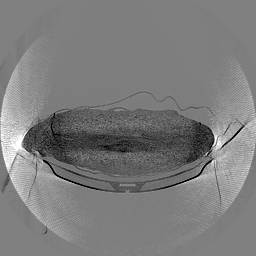

III-D Real Clinical Data Experiment

The experimental results on clinical head data are shown in Fig. 4. The reference images were reconstructed using the fast iterative shrinkage-thresholding algorithm (FISTA) with total variation regularization from non-truncated projection data. In the WCE reconstructions (Fig. 4(b)), severe truncation prevents accurate recovery of anatomical structures outside the FOV. Despite being trained solely on simulated data with a domain gap, all deep learning models can restore a substantial portion of the missing anatomy. Among them, the diffusion-based methods recover soft-tissue boundaries more faithfully than the conventional deep learning approach FBPConvNet, highlighting their stronger image generation capability. However, cDDPM reconstructions exhibit more noticeable noise than those from other methods, consistent with the simulated data results. The patchDiffusion model introduces artifacts within the FOV, likely due to its patch-wise processing strategy. While I2SB shares the same limitations as other diffusion models in perfectly restoring soft-tissue detail, it produces fewer residual noise patterns and fewer artifacts within the FOV boundaries. Overall, Fig. 4 demonstrates the strong efficacy of I2SB in reconstructing real CBCT data.